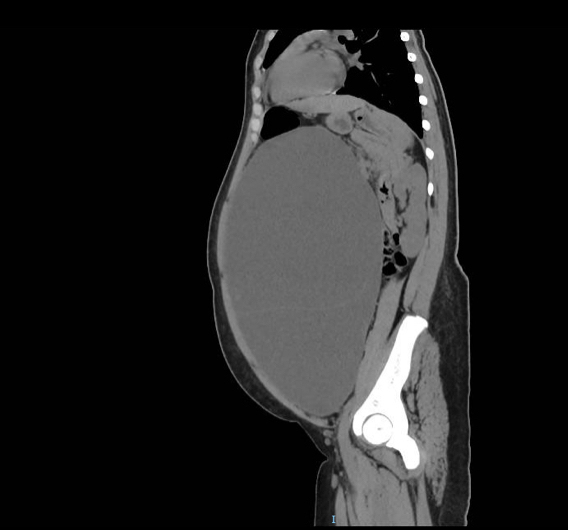

检查结果让母女俩大惊失色——B超影像清晰地显示,小敏的盆腹腔内竟然藏着一个巨大的肿物,几乎占据了整个腹腔。焦急万分的母女俩随即来到暨南大学附属第一医院妇科求助。

接诊医生高绿芬在详细了解病情并完善各项检查后,为小敏制定了周密的手术方案。术中抽出的囊内液体多达9.5升,相当于19瓶500毫升矿泉水的容量。幸运的是,术中快速冰冻病理结果显示:肿瘤为卵巢黏液性囊腺瘤,是一种常见的卵巢良性肿瘤。这个结果让所有人长舒了一口气,然而,代价也是沉重的——因为肿瘤发现太晚,体积过于巨大,已经完全侵蚀了她一侧的卵巢组织,医生不得不为她切除了一侧的卵巢。

影像图显示,小敏的腹部隆起如足月的孕妇。